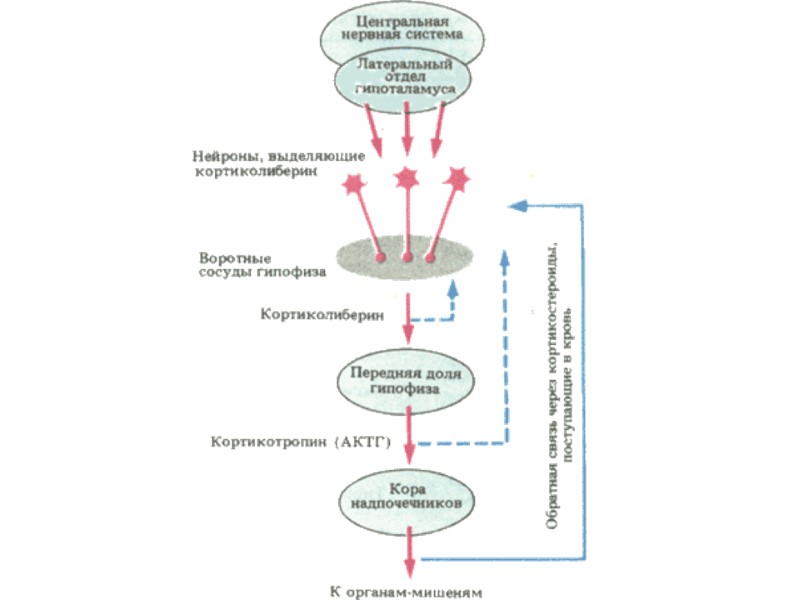

Гипоталамо-гипофизарно нейросекреторный комплекс – высший нейроэндокринный трансмиттер организма, координирующий эндокринную регуляцию метаболизма с работой ВНС и интегральными эмоционально-поведенческими реакциями лимбической системы. Состоит из: - Гипоталамус; - Нейрогипофиз; - Аденогипофиз

Группы биорегуляторов, продуцируемых гипоталамусом Либерины и рилизинг-факторы (тиролиберин, кортиколиберин …); Статины и ингибитинг-факторы (соматостатин, пролактостатин? ...); Нонапептиды (вазопрессин и окситоцин); Моноамины (дофамин, серотонин, гистамин …); Эндогенные опиоиды; Другие нейропептиды

Гипофиз – орган, обеспечивающий процессы метаболизма и репродукции организма. - Аденогипофиз; - Нейрогипофиз

Аденогипофизарные клетки Соматотропы – 40 – 50 % (СТГ); Лактотропы – 20 % (Пролактин); Тиротропы – 6 % (ТТГ); Гонадотропы – 3 – 4 % (ЛГ и ФСГ); Хромофобы – 20 % ??? Кортиколипотропы – 15 – 20 % (ПОМК – пропиомеланокортин → МСГ, АКТГ, α- и β- эндорфины, N-концевой гликопептид…)

АКТГ – как гормон стресса Инсулиноподобное и стимулирующее СТГ действие; Липолитический эффект; ↑ - потребление АК в мышцах и внутриклеточный транспорт глюкозы; ↓ - обранование мочевины и распад ГКС в печени; Поведенческие реакции; Противовирусный эффект

Эффекты глюкокортикостероидов Углеводный обмен: стимуляция глюконеогенеза и гликогенолиза; Липидный обмен: ускорение липолиза в конечностях и ускорение липогенеза на лице и туловище; Белковый обмен: анаболическое действие в печени и катаболическое в других органах; Иммунная система: иммунодепрессанты в высоких дозах; Воспаление: выраженный противовоспалительный эффект; Обмен натрия и калия: задерживают в организме натрий и способствуют выведению калия; Кроветворная система: стимуляция гранулоцитарного и эритроидного ростков гемопоэза …